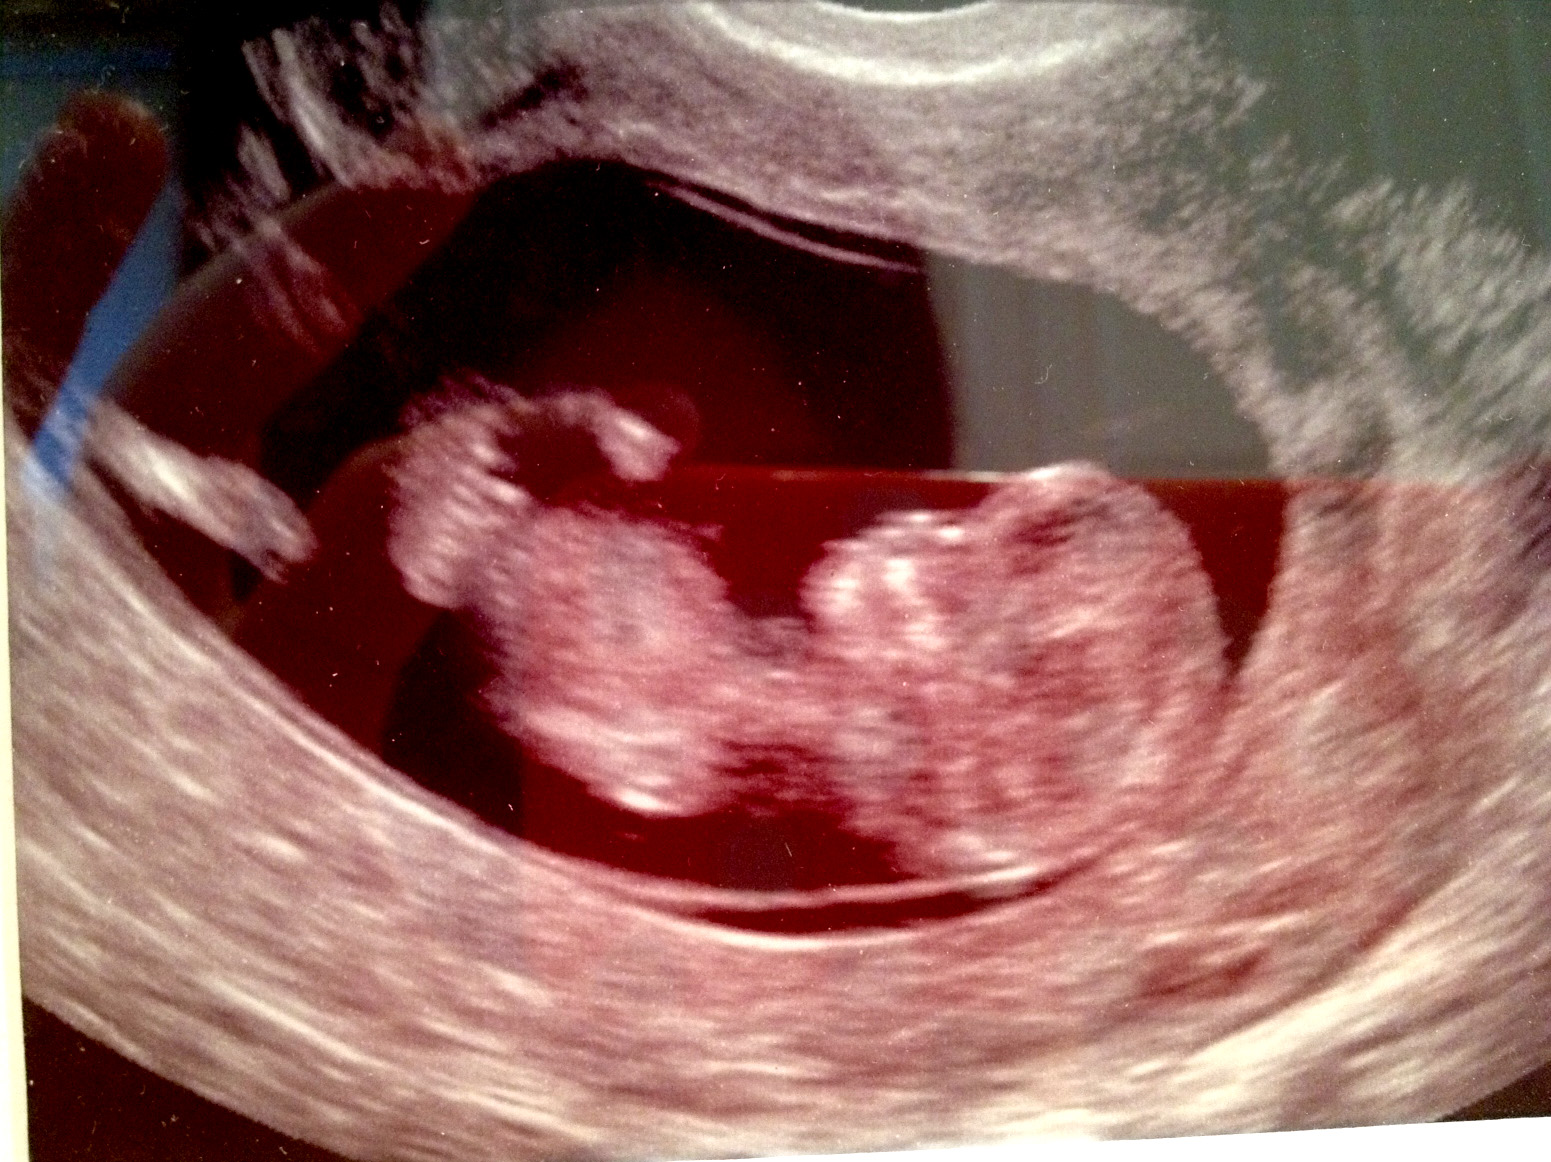

Here's another photo, nub? Not so much?Attachment 4228

I really would have to guess boy

I am going to guess Boy as well.

I'm going to say girl... nub not very boyish and angle is parallel.

I can't tell!